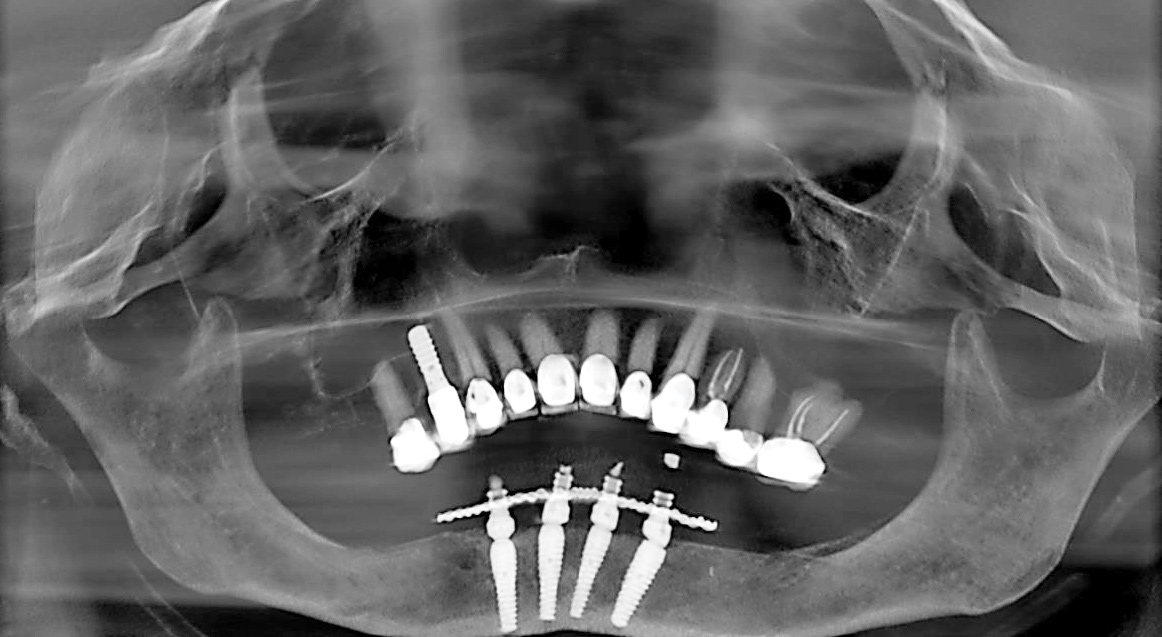

Fig 16. Presurgical panoramic radiograph of a patient receiving All-on-4–style treatment with multiple dental implants requiring explantation. Note the dental implants in the mandibular right quadrant that are compromising the inferior alveolar nerve.

Figure 16

Fig 17. Postsurgical panoramic radiograph of the patient from Figure 16 following All-on-4–style dental implant treatment.

Figure 17

Removal of Dental Implants

All-on-4–style treatment sometimes requires the removal of previously placed dental implants (Figure 16 and Figure 17). Although some of these implants may have biologic complications such as peri-implantitis that may ease the removal process, most previously placed implants requiring explantation by the author have been firmly osseointegrated. Previously placed dental implants are not typically suitable for All-on-4–style surgeries because the platforms were placed to a level in accordance with the natural teeth. Although this is perfectly suitable when natural teeth are present, these platform positions are too coronal for All-on-4–style treatment. Furthermore, previously placed dental implants preclude the ability for adequate bone reduction. In the author’s experience, using previously placed dental implants for All-on-4–style treatment often results in restorations of inadequate thickness that have a propensity for fracture due to the coronal position of the platforms and the lack of bone reduction. As such, the author routinely removes previously placed dental implants when performing All-on-4–style treatment.

Dental implant removal for All-on-4–style surgery is particularly concerning because of the need for immediately loading a prosthesis. Dental implants requiring removal are typically the same diameter as the implants intended for use in the All-on-4–style surgery. If the implants can be removed with a high-torque dental implant retrieval tool (Figure 18), bone is preserved and a dental implant of at least the same diameter and length can be used for the All-on-4–style treatment. Should the implant retrieval tool fail to explant the previously placed dental implant, trephination is required. The bone loss subsequent to trephination of a dental implant may eliminate the possibility of placing a new implant and thus compromise immediate loading of a transitional prosthesis. As has been reported by others,43-45 the author has had a high degree of success in removing previously placed dental implants with high-torque retrieval tools. In cases in which trephination was required, the author has replaced the previously existing implants with new implants of both wider and longer dimensions.